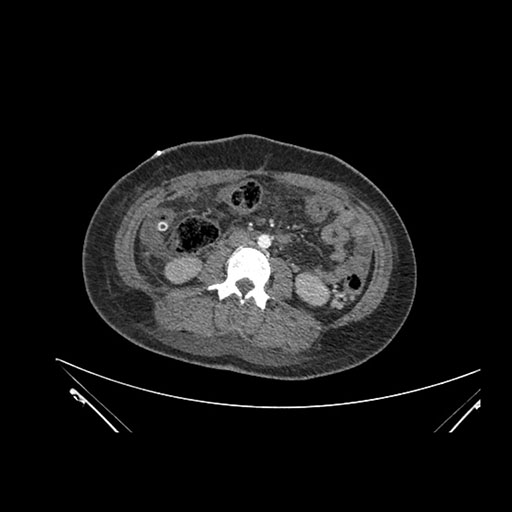

Imaging Analysis

Look through the patient's CT scan to identify any areas of concern for the necessary procedure.

Coronal Arterial

Based on initial findings, which issue(s) would you be most concerned about?